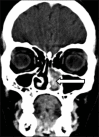

Nasal lobular capillary hemangioma is a rare benign tumor of the paranasal sinuses. This lesion is believed to grow rapidly in size over time. The exact etiopathogenesis is still a dilemma. We discuss a case of nasal lobular capillary hemangioma presenting with a history of epistaxis. Contrast enhanced computed tomography of paranasal sinuses revealed an intensely enhancing soft-tissue mass in the left nasal cavity and left middle and inferior meati with no obvious bony remodeling or destruction. We present imaging and pathologic features of nasal lobular capillary hemangioma and differentiate it from other entities like nasal angiofibroma.